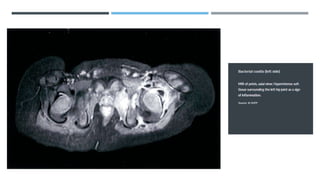

Bacterial coxitis (septic arthritis of the hip)

Bacterial coxitis is an orthopedic emergency!